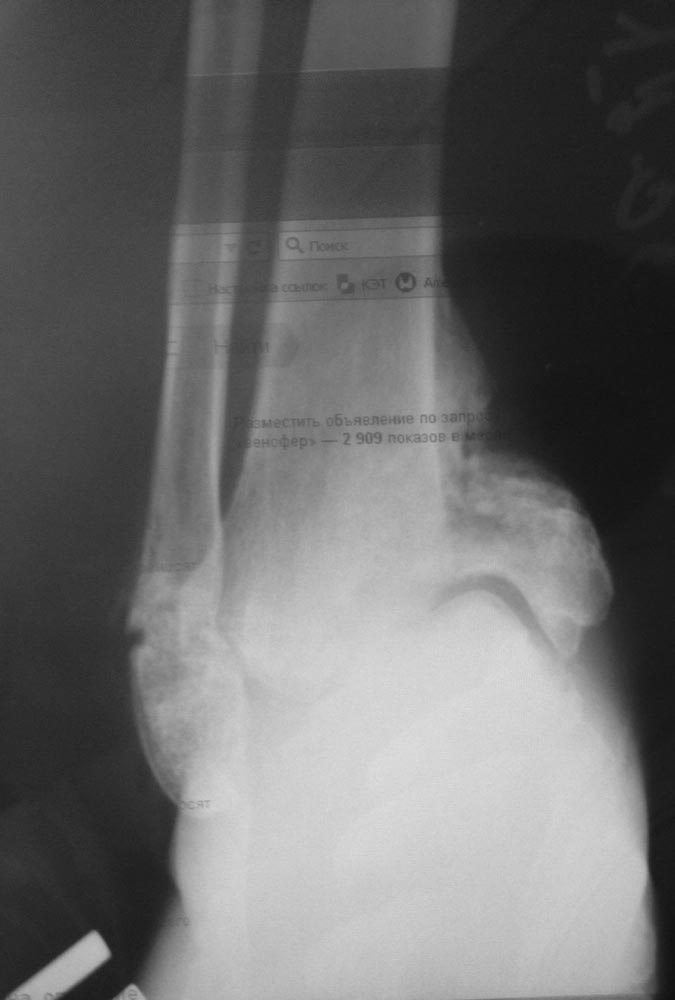

Здравствуйте, коллеги! У пациентки 28 лет СД 1 типа, остеоартропатия стопы, полинейропатия. Перелом лодыжек и пяточной кости произошёл, по-видимому, спонтанно, без явной травмы3 месяца назад. Сейчас признаки консолидации лодыжек в порочном положении - вн. лодыжка смещена краниально, стопа в варусе. Аваскулярный некроз таранной кости с частичным остеолизом.Возникает мысль о необходимости артродеза голеностопного и подтаранного суставов штифтом.В настоящее время СД компенсирован.

PS извините за качество снимка, пока располагаю только таким.